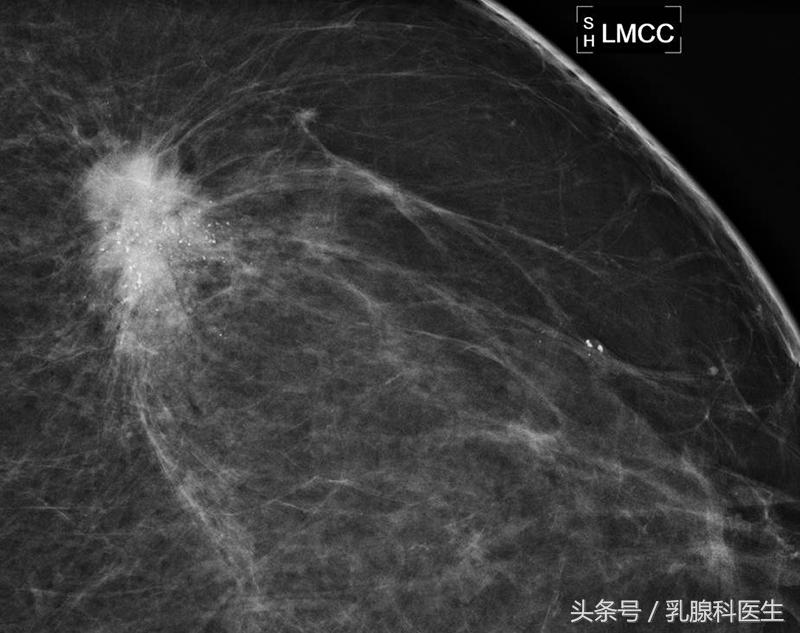

BI-RADS 5:高度怀疑恶性(几乎肯定的恶性),临床应采取适当措施。这一类病变的恶性可能性大于等于95%。

BI-RADS 6:已活检证实为恶性,应采取积极的治疗措施。

BI-RADS 1或者2:定期复查即可。BI-RADS 3:一般考虑为良性病变,但不能完全排除肿瘤。建议3个月后复查。BI-RADS 4:我推荐穿刺活检。BI-RADS 5:不要犹豫,尽快手术切除活检。⑹BI-RADS 6:和您的医生充分沟通,根据自身情况制定最佳的治疗方案。